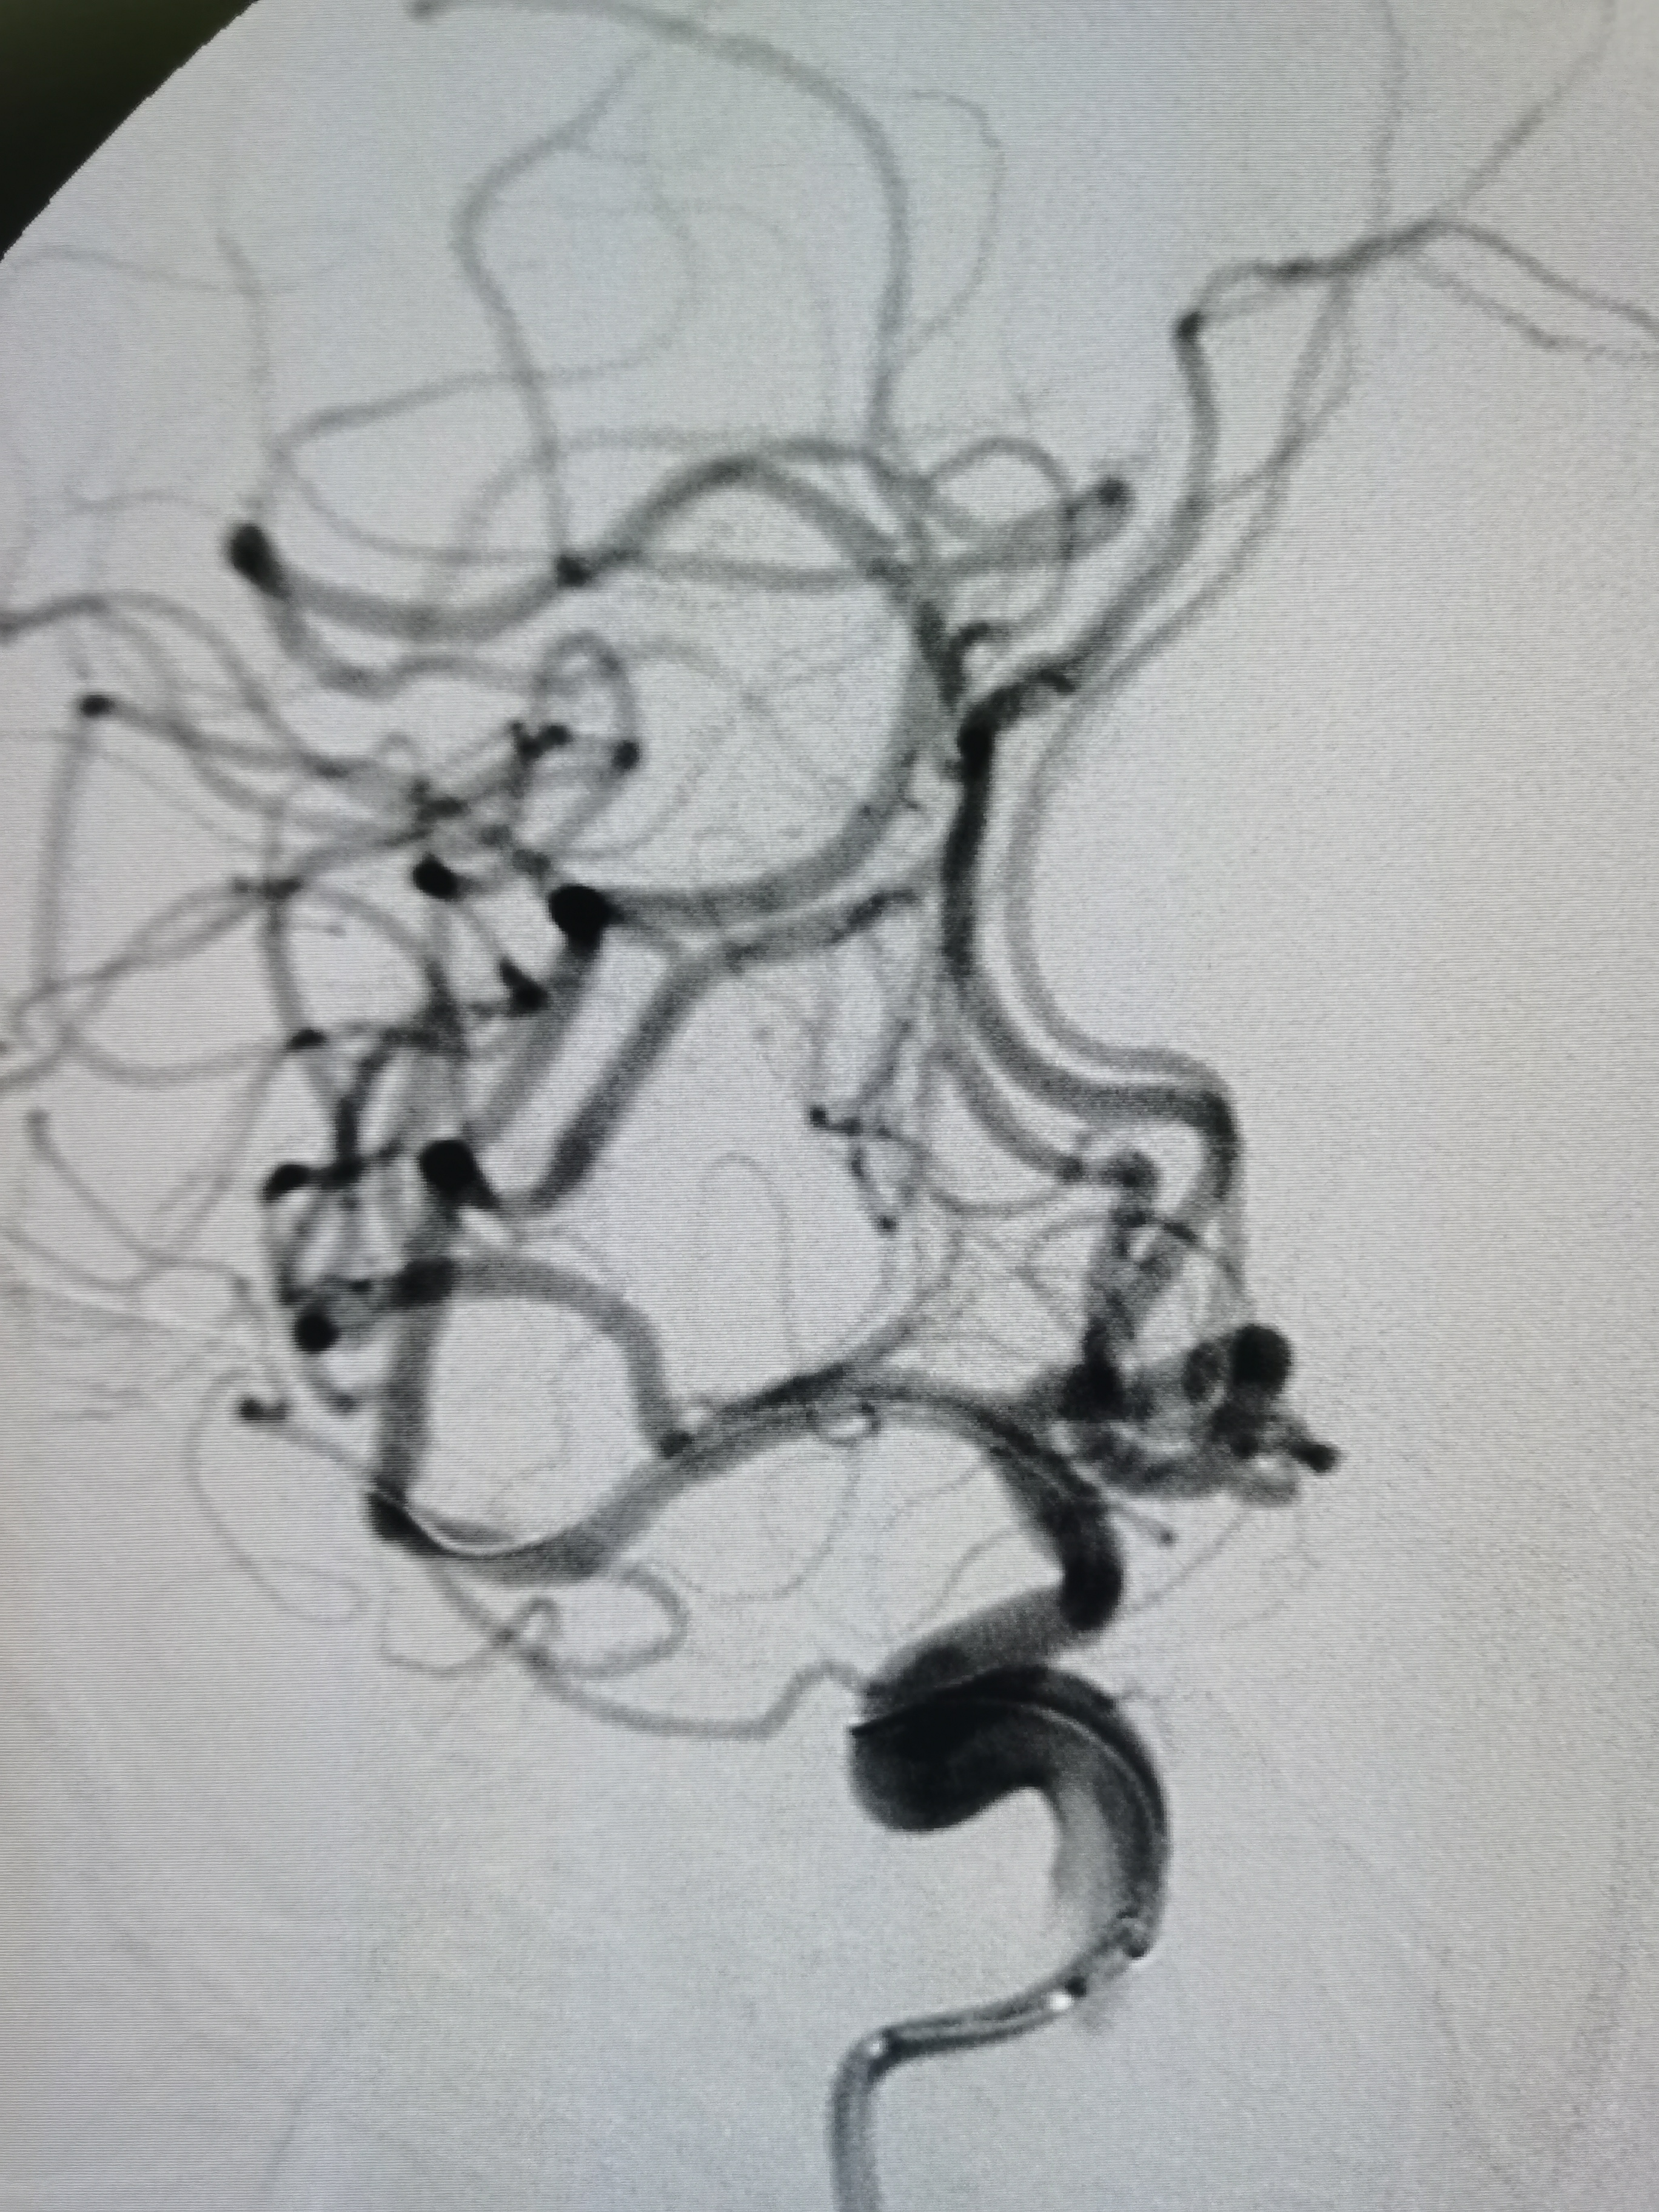

8F导引导管+6F中间导管建立通路,微导丝携微导管顺利通过病变,交换Transend300导丝,路径图下送入2.5/15颅内扩张球囊,缓慢加压至6atm。

在球囊到位前后分别给予导管内推注替罗非班行穿支冲洗,避免扩张过程中豆纹动脉闭塞。

球扩后造影见狭窄解除,豆纹动脉显影良好,远端血供改善,未见夹层征象。